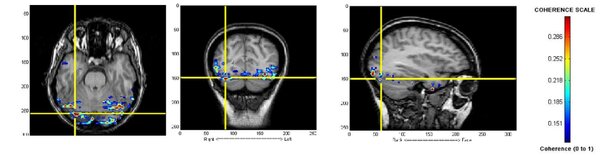

Identification of microwave-related changes in tissue using an ultrasound scan

Shariff et al. | Apr 24, 2024

Image credit: Shariff and Shariff 2024

Microwave energy (ME) is used in the medical field to denature protein structures, resulting in inactivation or destruction of abnormal cells. Identifying the extent of destruction of abnormal tissue (cancer tissue or tissue with abnormal electrical activity) is essential for accomplishing successful therapy and reducing collateral damage. Our study was an ex vivo assessment of the changes on ultrasound scans (US) in chicken tissue exposed to ME. We hypothesized that any changes in tissue structures would be recognized on the reflected ultrasound waves. Ultrasound scans of tissues change with exposure to microwaves with increasing reflection of ultrasound waves. With exposure to microwaves, surface level brightness on the ultrasound scans increases statistically significantly. The findings could be used in heat related (ME and radiofrequency) procedures where clinicians would be able to actively assess lesions in real-time. Further studies are required to assess changes in tissue during active exposure to different types of energies.